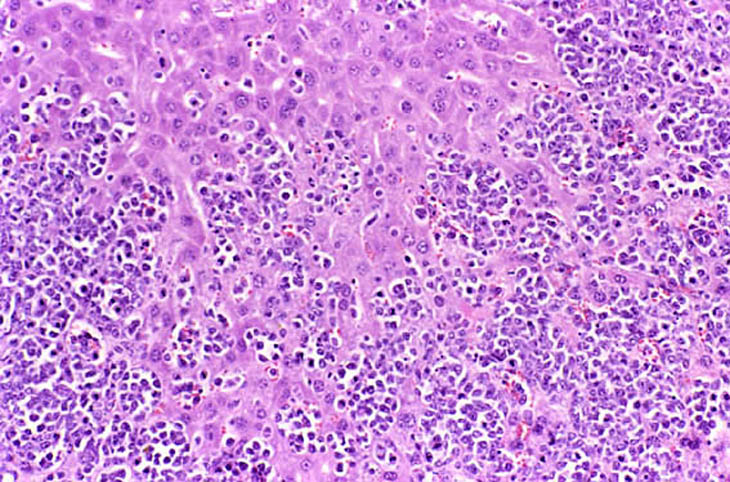

Infiltration of malignant lymphocytes in a liver from an adult mouse.

Severe infiltration of the liver by malignant lymphocytes. Hepatocytes visible in the lower right corner.